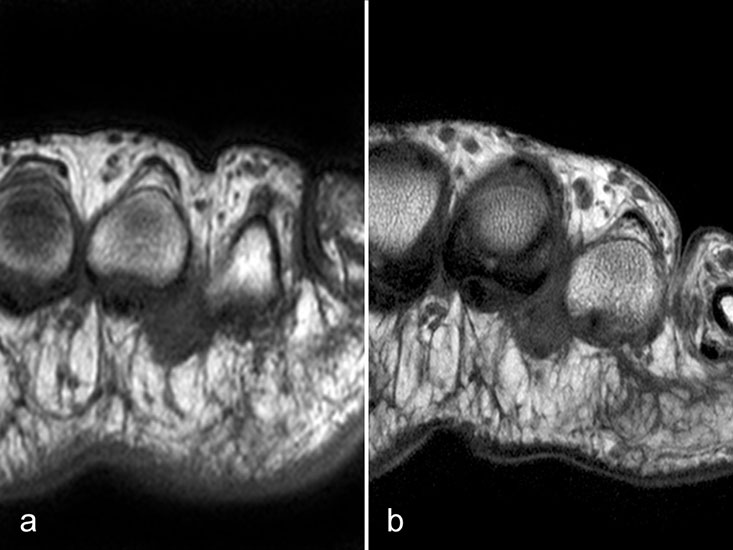

Intermetatarsale Bursitis

Intermetatarsale Bursitis bei rheumatoider Arthritis mit Erguss (a) und deutlicher Synovialitis in mehreren Schleimbeuteln (b).

Abbildung 13

Zwischen den Metatarsaleköpfchen befinden sich kleine Schleimbeutel, die in der Regel MR-tomographisch nicht zu identifizieren sind. Sie werden erkennbar, wenn sie zarte Flüssigkeitsstreifen enthalten, was noch nicht als pathologisch zu werten ist. Eine signifikante Distension und vor allem eine verstärkte Kontrastmittelanreicherung sind Ausdruck einer Bursitis. Die isolierte Bursitis intermetatarsal ist selten und stets hochverdächtig für das Vorliegen einer rheumatischen Grunderkrankung (Abb. 13).

Häufig sind intermetatarsale Bursitiden als Begleitphänomen bei Rupturen oder Degenerationen der plantaren Platte und auch bei Morton-„Neuromen“.